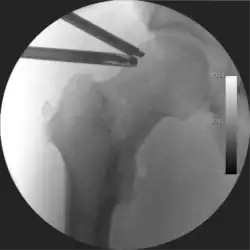

![]() Intraoperative fluoroscopic image during an arthroscopic resection of a cam lesion of the femur. The upper instrument is the arthroscope (viewing device), while the lower is the high-speed burr used for reshaping the bone. |

Standard arthroscopic treatment of symptomatic cam FAI involves debridement (resection) or repair of any labral [10] and chondral injuries [11] in the central compartment of the hip, and subsequent reshaping of the head-neck junction of the upper femur (osteochondroplasty) in the peripheral compartment [12][13] using high-speed motorised burrs that are similar in design to a dentist's drill (see fig. 9).